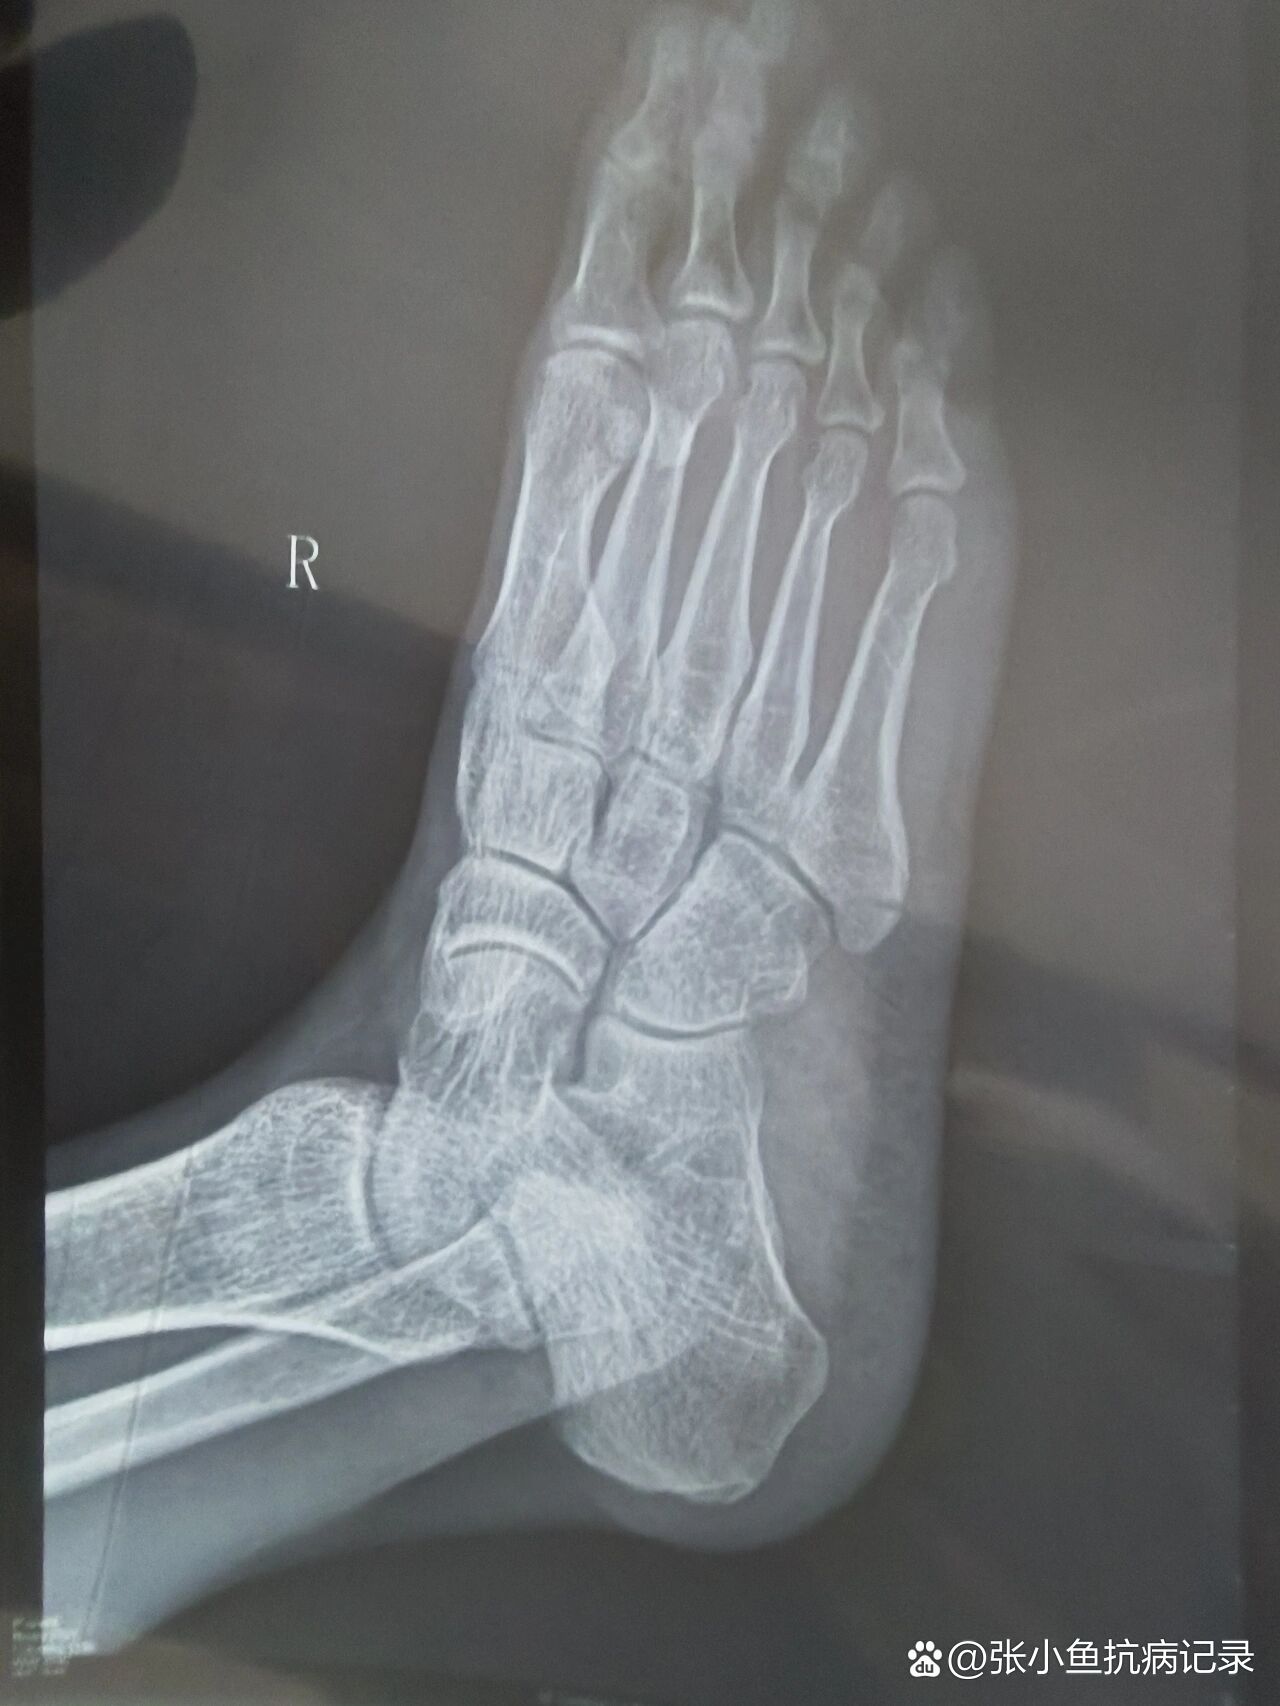

正确叫法是"右足第5跖骨粗隆骨折"

第五跖骨骨折1个月 从2月13到3.14,骨折30天了,满一个月了.